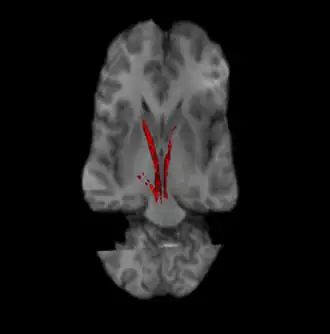

![]() Nigrostriatal pathway (Left and Right in red). | |

The nigrostriatal pathway is a bilateral dopaminergic pathway in the brain that connects the substantia nigra pars compacta (SNc) in the midbrain with the dorsal striatum (i.e., the caudate nucleus and putamen) in the forebrain. It is one of the four major dopamine pathways in the brain, and is critical in the production of movement as part of a system called the basal ganglia motor loop. Dopaminergic neurons of this pathway release dopamine from axon terminals that synapse onto GABAergic medium spiny neurons (MSNs), also known as spiny projection neurons (SPNs),[1][2] located in the striatum.